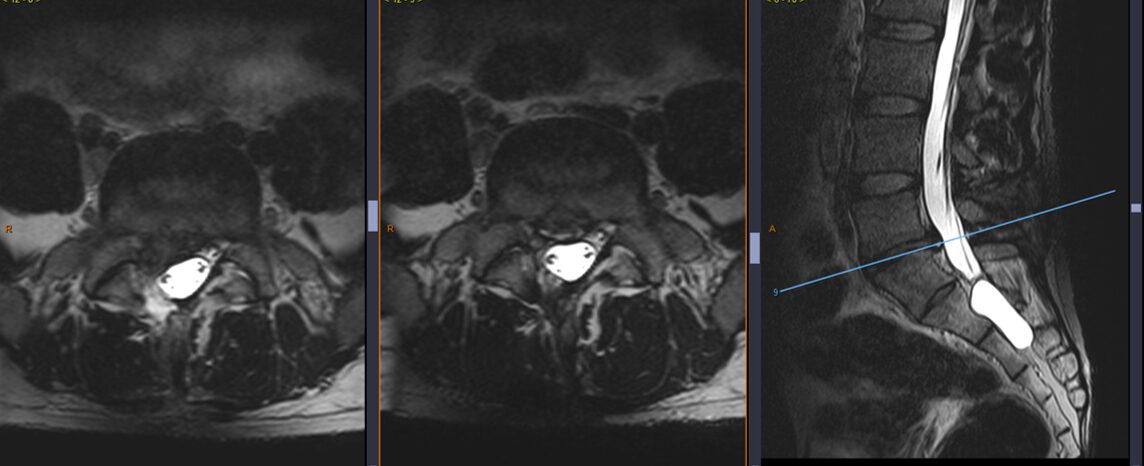

Hernie discale L5S1 avant et après chirurgie